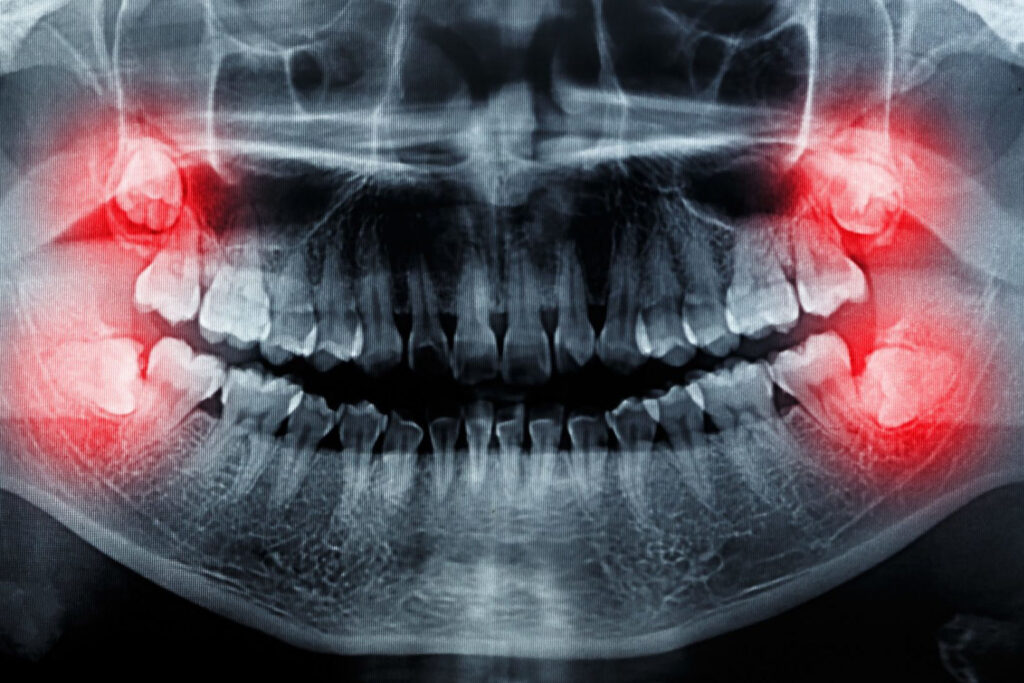

The badly lying wisdom teeth cause various problems that you perceive of course. If you have no symptoms, it is best to ask your dentist about their condition. Regular x-rays can follow their condition, and so they can be coordinated with the other teeth.

The problems come from the fact that our jaw has become anatomically smaller with the progress of evolution, as a result of which these teeth no longer have any space. For most young people – about three of four – there is not enough anatomical space for wisdom teeth in the row so sooner or later the majority of the adult population will encounter difficulties.

In the lucky case, the wisdom teeth begin to grow and break. The worst situation occurs when they can not break through the gums. There are countless possibilities between these two extremes.

Tooth removal is recommended when the wisdom tooth is positioned so that there is no chance for it to break through and causes recurrent inflammation and pain. If other ailments occur, such as tooth decay, or because of difficult cleaning gingivitis, it is also worth pulling them out.

It is also rare that an X-ray suspects a sometimes malignant change, in which case it is of course important to remove it as soon as possible.